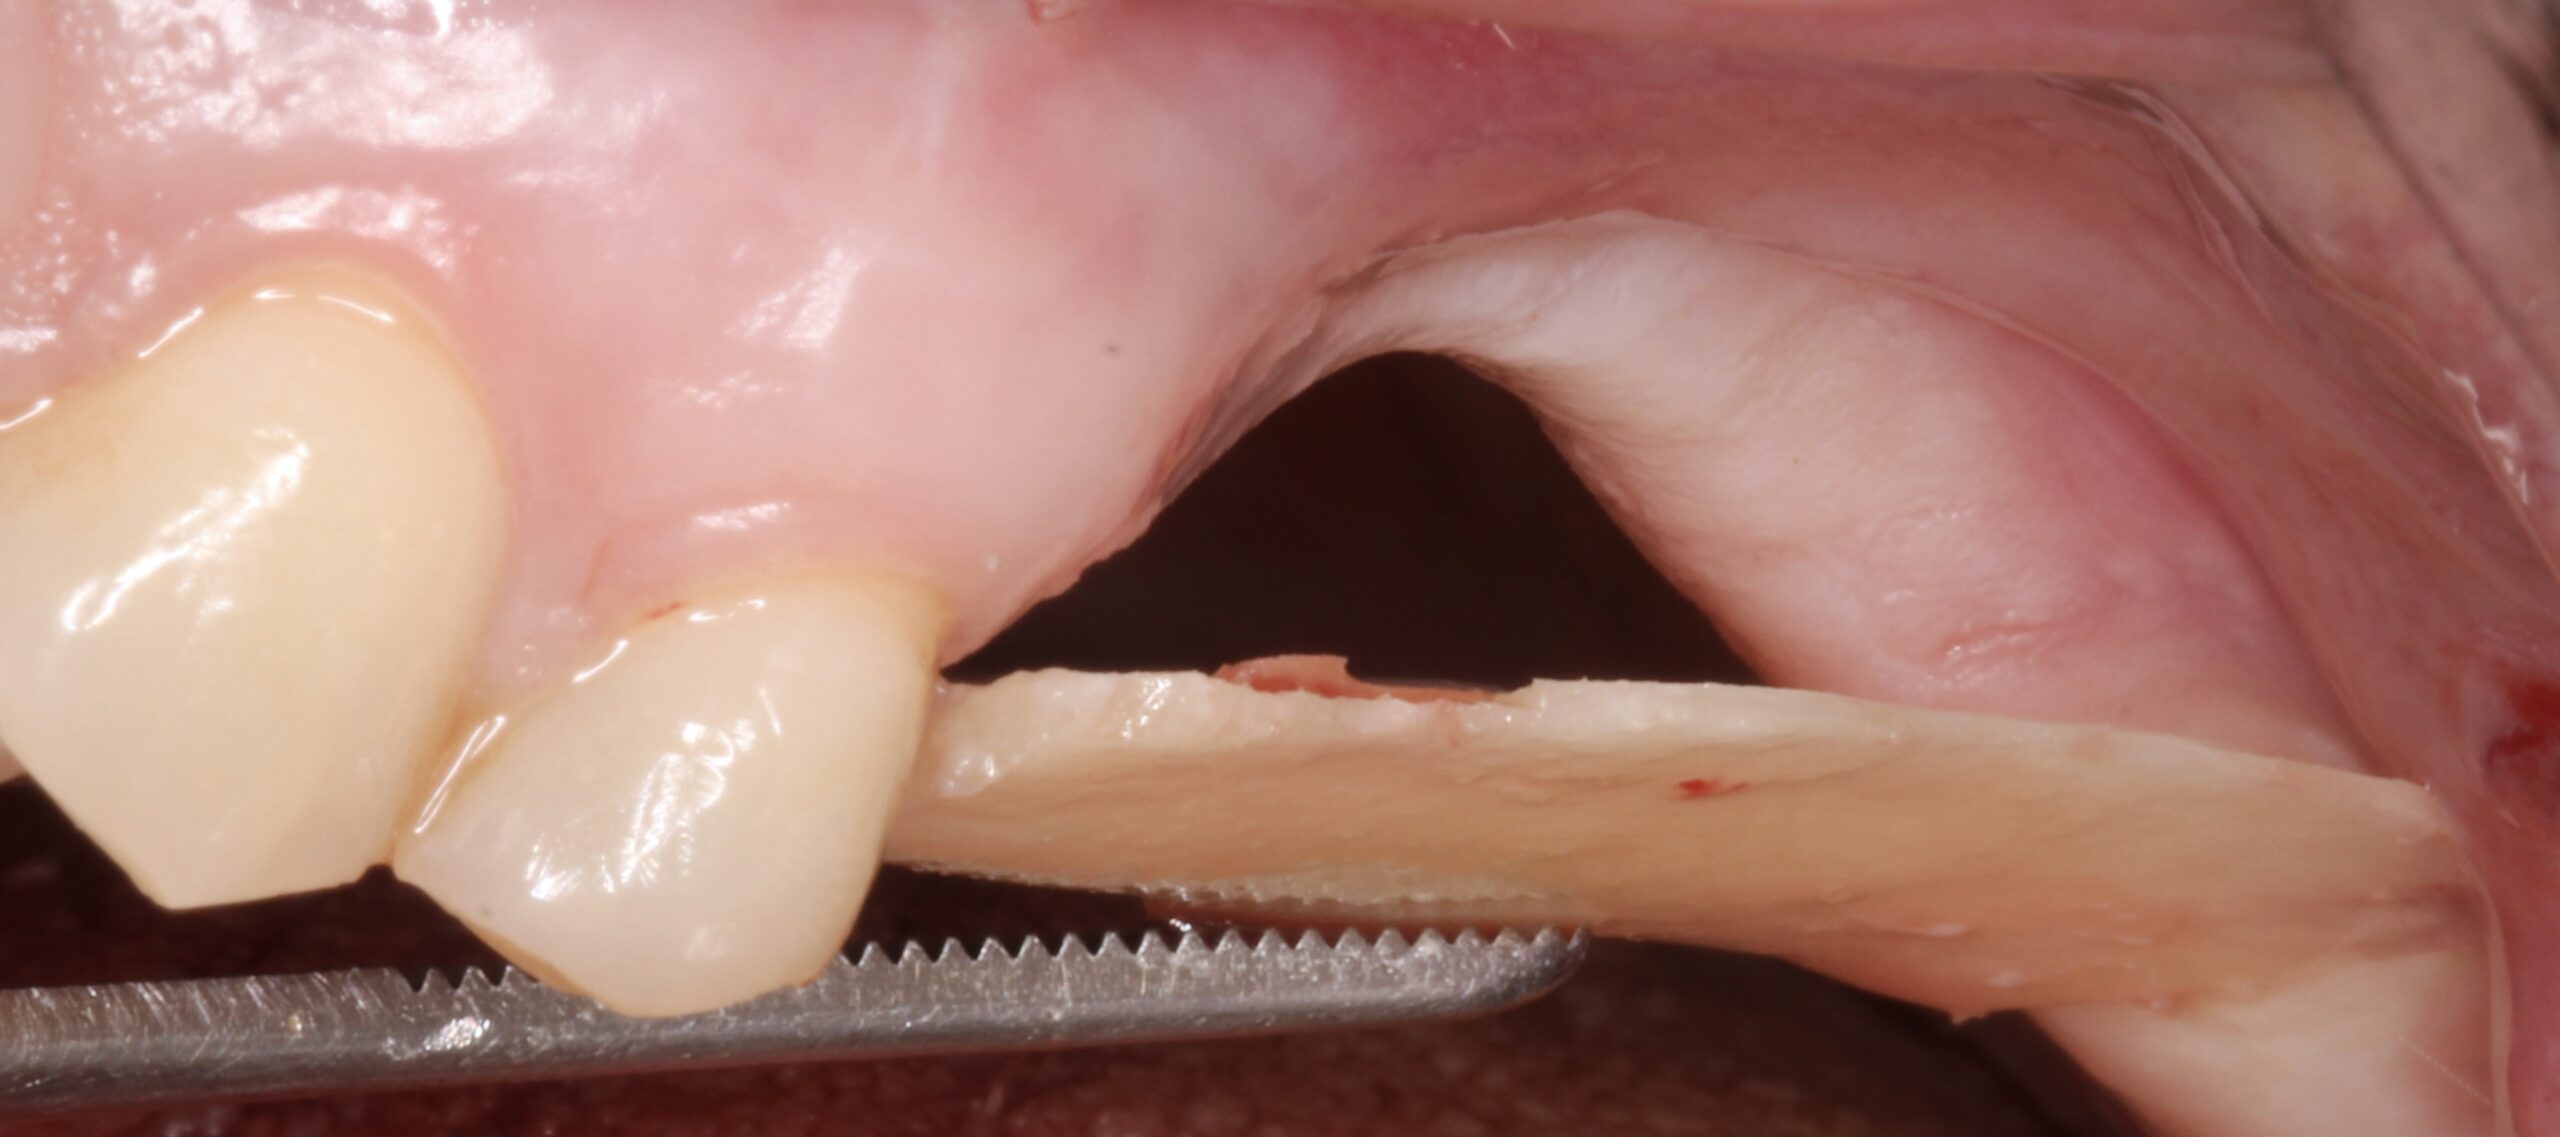

Figure 1.

Palatal view of the left posterior maxilla showing severe bone atrophy. Full thickness incision to expose the alveolar ridge.